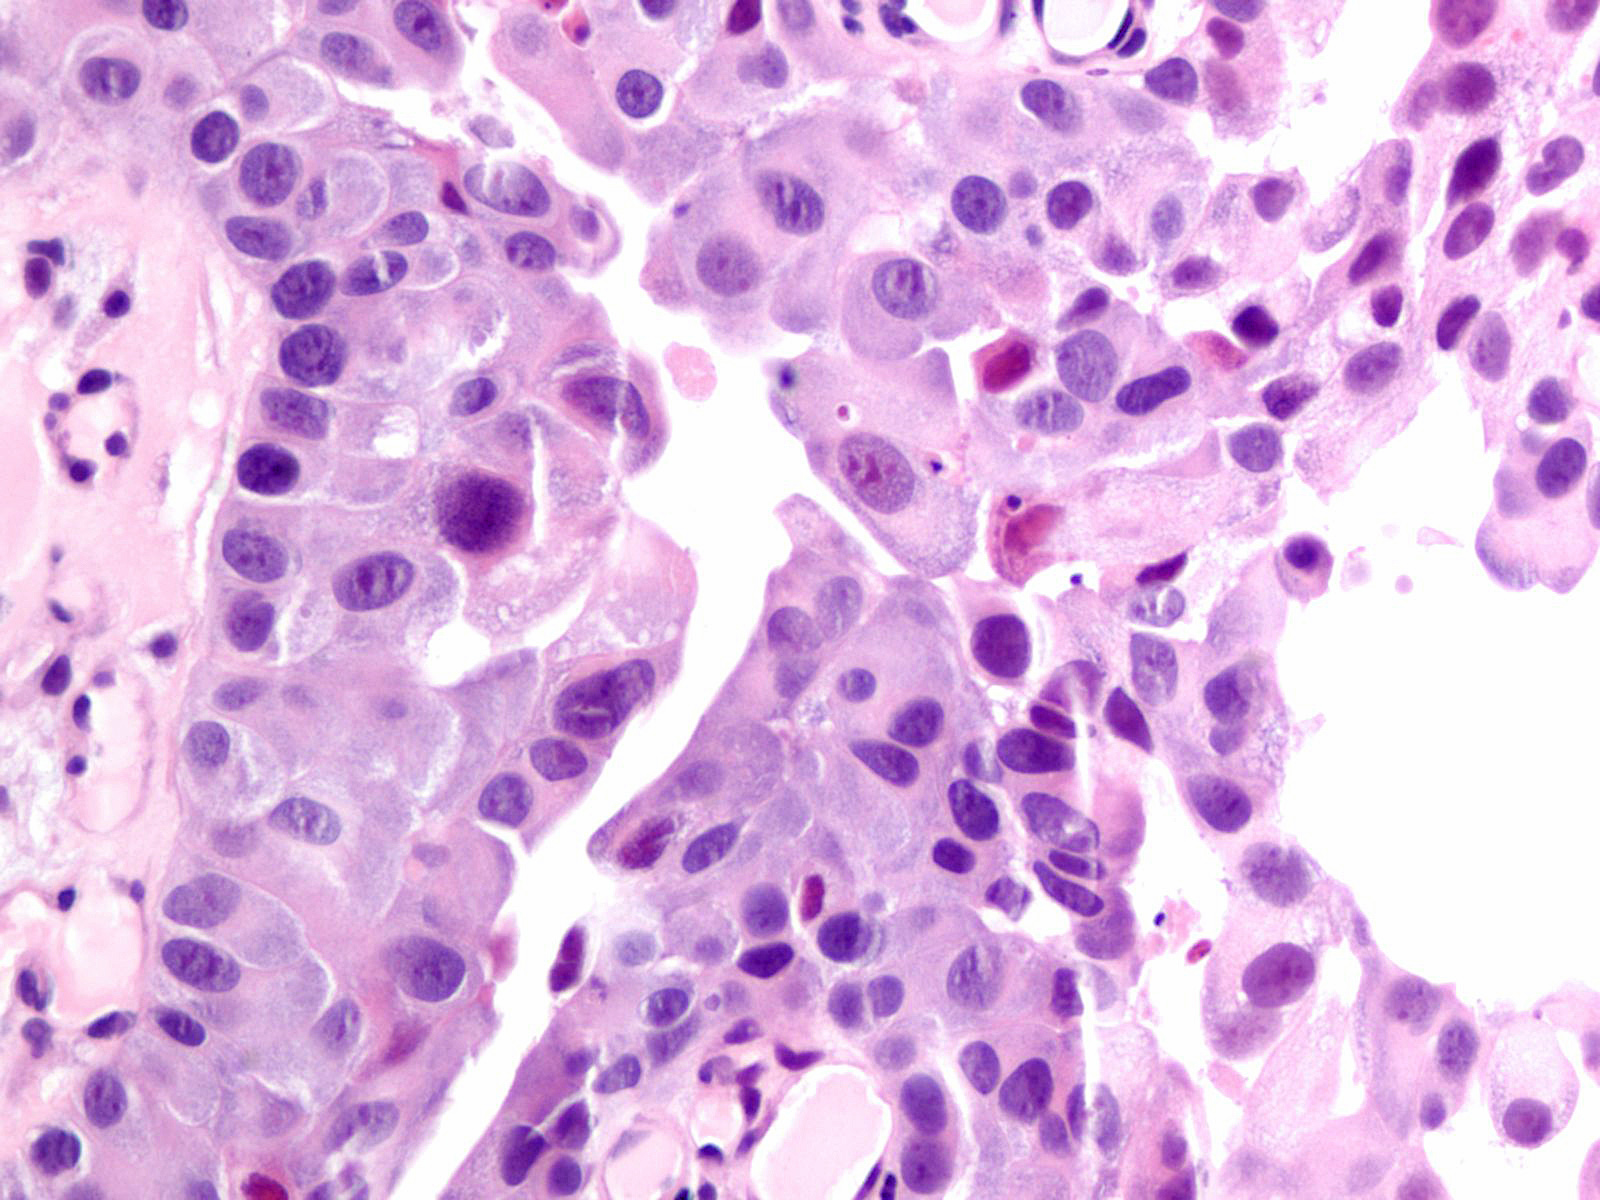

Consensus grade: High-grade papillary urothelial carcinoma (HG-PUC)

Lesion shows marked variation in nuclear size, shape and chromatin. Architecturally, cells appear loosely cohesive and the epithelium is disorganized. Mitotic figures are seen.